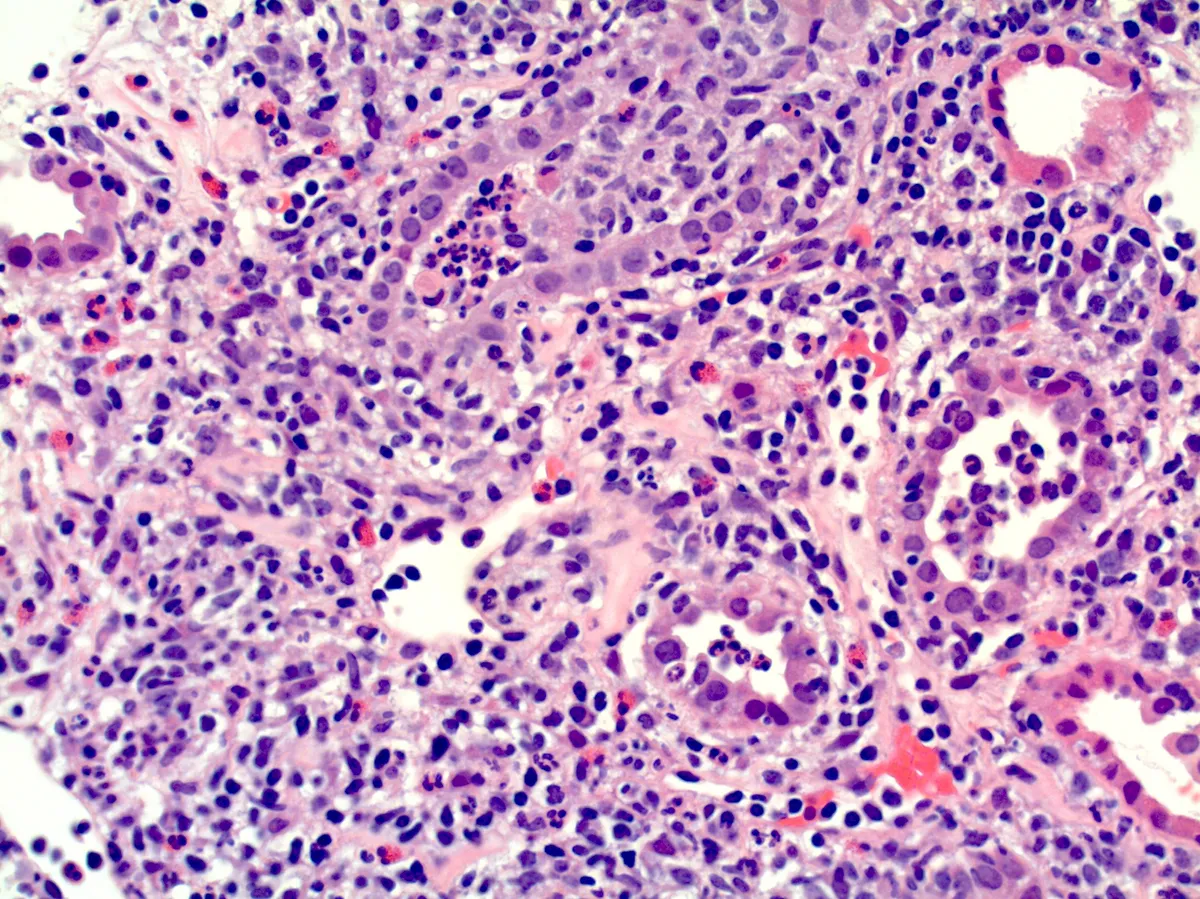

IRA + Icterícia: Um Caso que Exige Investigação Detalhada

IRA + Icterícia: Um Caso que Exige Investigação Detalhada